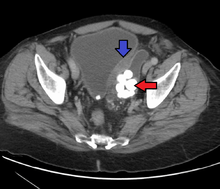

- Bladder diverticulum: Balloon-like growths on the bladder commonly associated with a chronic outflow obstruction, such as benign prostatic hyperplasia in older males. Usually found in pairs on opposite sides of the bladder, bladder diverticula are often surgically removed to prevent infection, rupture, or even cancer.